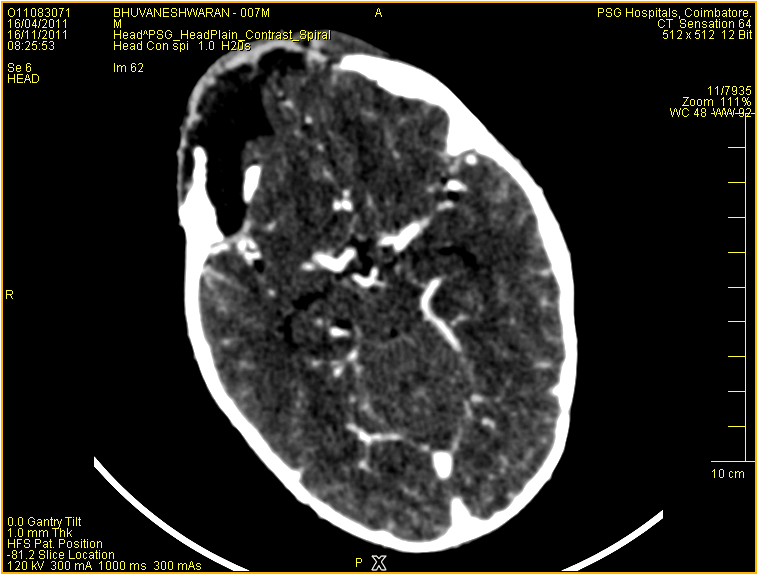

A Rare Case of Right Frontal and Ethmoidal Bony Deformity With Schizencephaly

Agenesis of skull bones, schizencephalyAbstract